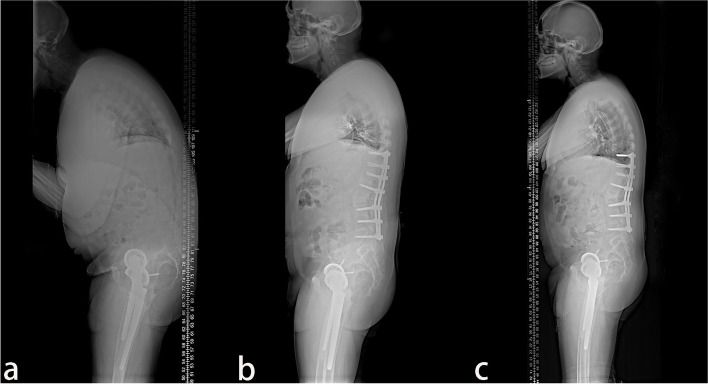

A total of 38 patients with AS combined with thoracolumbar kyphosis were successfully treated by PSO, with a mean follow-up time of 26.9 ± 11.9 months. There were 30 males and 8 females with a mean age of 41.6 ± 7.1 years. Twenty patients consisted in the lumbar lordosis group and 18 patients in the lumbar kyphosis group, with a mean operation time of 289.4 ± 123.2 min and 267.8 ± 96.8 min (P > 0.05), respectively. The patients were further subdivided into the lumbar lordosis T12 group (Fig. 1) with 11 patients, the lumbar lordosis L1 group (Fig. 2) with 9 patients, the lumbar kyphosis L2 group (Fig. 3) with 10 patients, and the lumbar kyphosis L3 group (Fig. 4) with 8 patients.

Fig. 3.

A 39-year old male patient. a The preoperative X-ray showed that the parietal vertebrae were located at T10, which belonged to the lumbar kyphosis group. b Single-segment pedicle subtraction osteotomy (PSO) was conducted at L2. Lumbar lordosis, global kyphosis, and sagittal vertical axis improved from the preoperative 8°, 78°, and 317.39 mm to –47°, 53°, and 60.47 mm, respectively. c At the last follow-up in the 28th-month post-operation, no apparent orthopedic loss was observed, and lumbar lordosis, global kyphosis, and sagittal vertical axis were –56°, 48°, and 55.56 mm, respectively